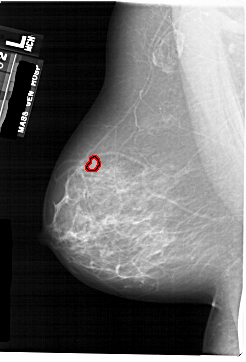

A_1742_1.LEFT_MLO

LEFT_MLO LINES 6871 PIXELS_PER_LINE 4666 BITS_PER_PIXEL 12 RESOLUTION 43.5 OVERLAY

FILE: A_1742_1.LEFT_MLO.OVERLAY

TOTAL_ABNORMALITIES 1

ABNORMALITY 1

LESION_TYPE MASS SHAPE LOBULATED MARGINS CIRCUMSCRIBED

ASSESSMENT 4

SUBTLETY 2

PATHOLOGY BENIGN

TOTAL_OUTLINES 1

BOUNDARY